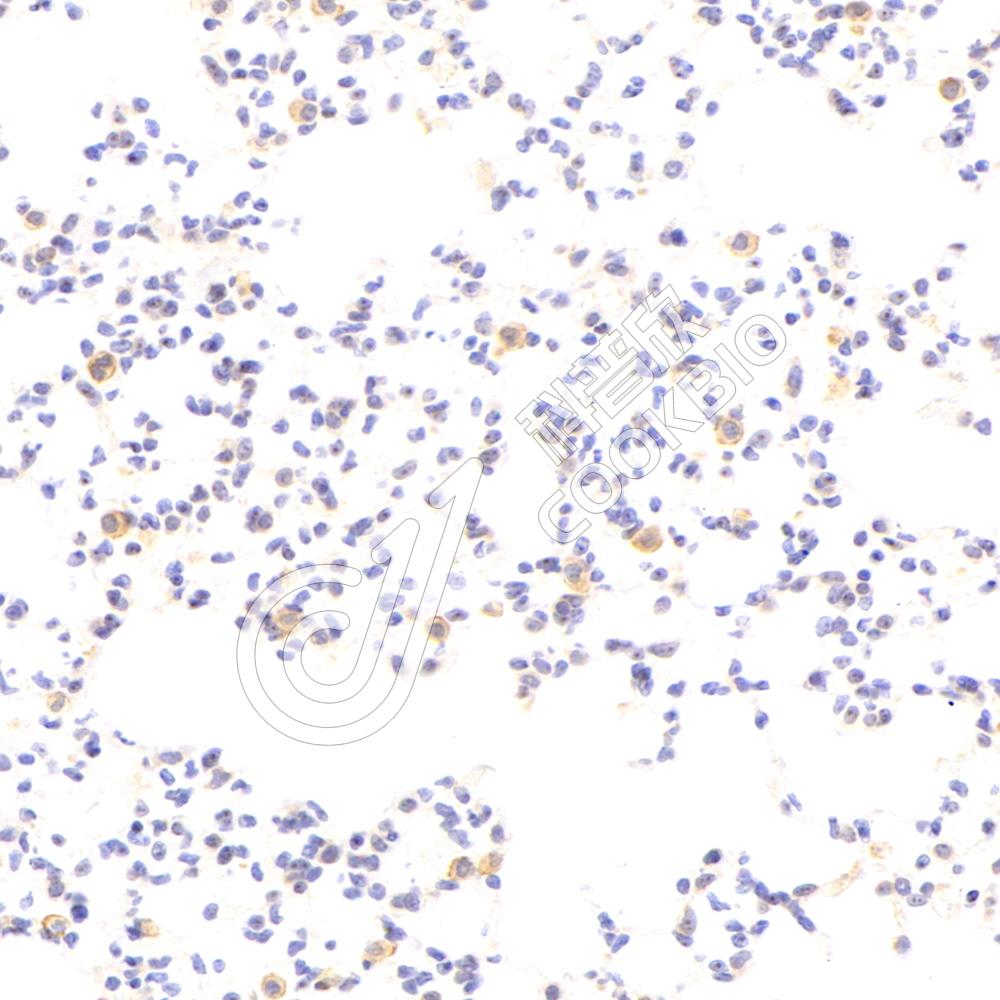

IHC检测FCN1/M-Ficolin蛋白(货号 K1340848).

样品: 小鼠肺, 4%多聚甲醛 (货号KSG1101) 固定12-24小时.

抗原修复: 柠檬酸抗原修复液(干粉, pH 6.0) (KSG1201), 98℃, 20分钟.

—抗: 1: 2300稀释, 4℃ 孵育过夜.

二抗: S-vision免疫组化多聚二抗(山羊抗兔),即用型 (货号KB3906), 室温孵育20分钟.